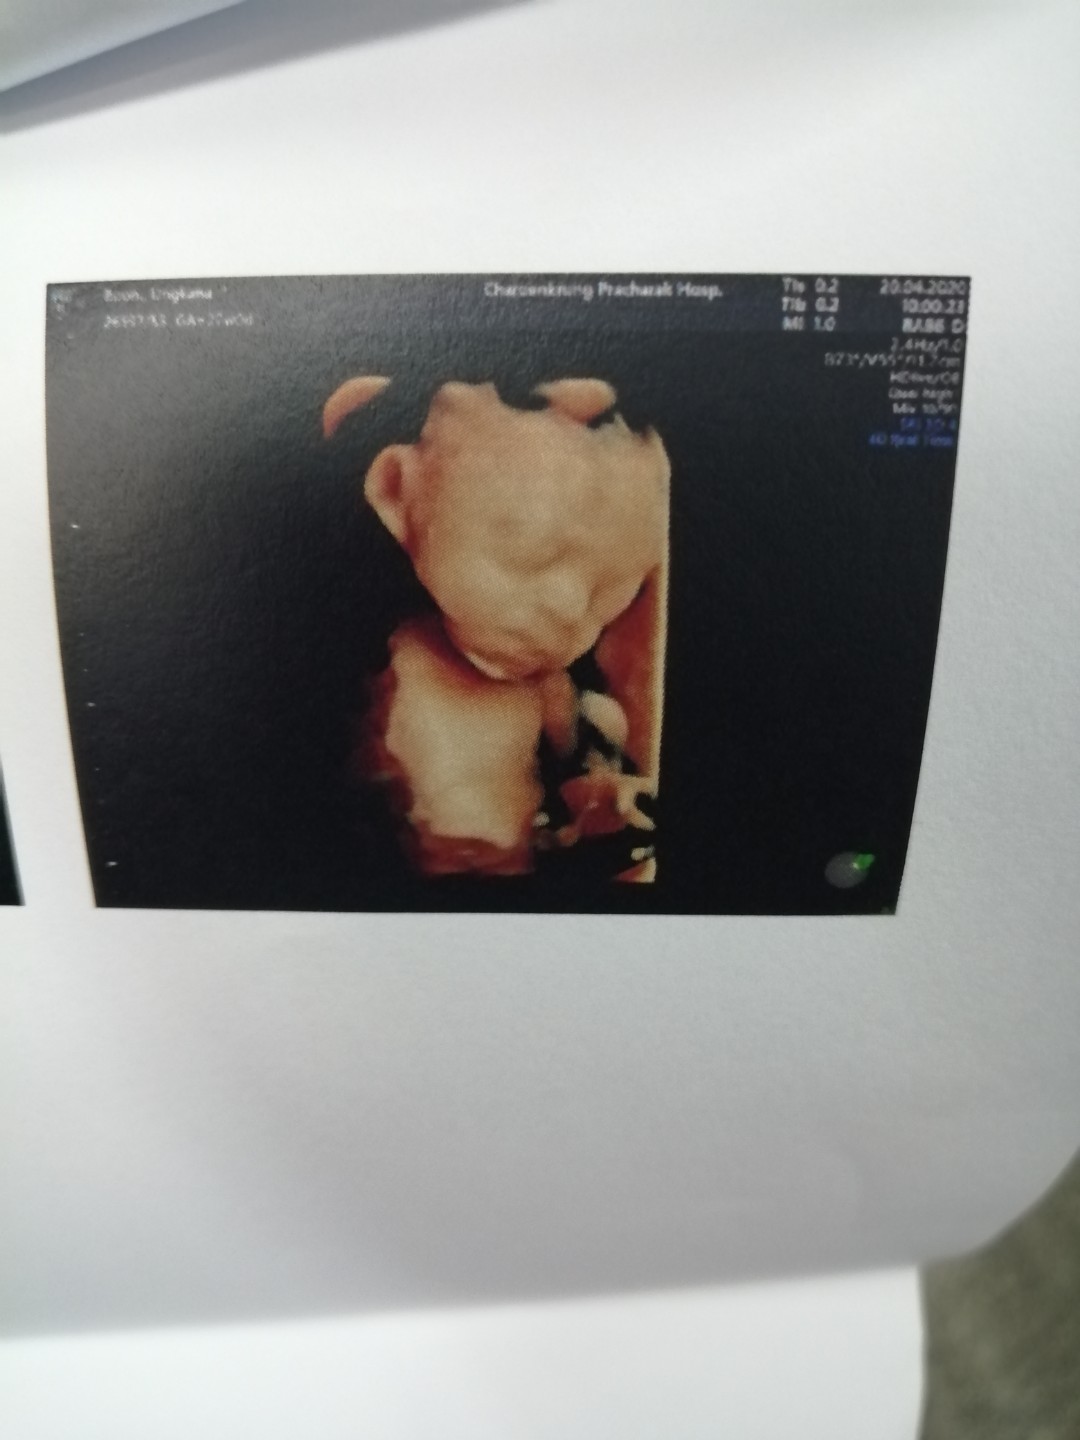

เห็นหน้าชัดกันมั๊ยคะ บ้านนี้ เอามือบังตลอดเลยค่า หมอเขย่าท้องก็แล้วไม่เอาออกเลยย ??

ตอน นั้นประมาณ6เดือน..ตอนนี้36wแล้ว

ซาวด์ตอน27weekจ้า ตอนนี้33+2weekแล้ว